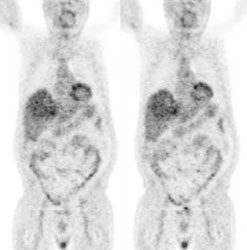

Pancreatic cancer: The patient shown below had a history of thyroid cancer and was being evaluated for a large neck mass. The PET scan revealed intense uptake in the abdomen anterior to the right kidney (black arrows). Subsequent CT imaging revealed a large mass in the pancreatic head (white arrows). There is atrophy of the remainder of the pancreas and dilatation of the pancreatic duct. |